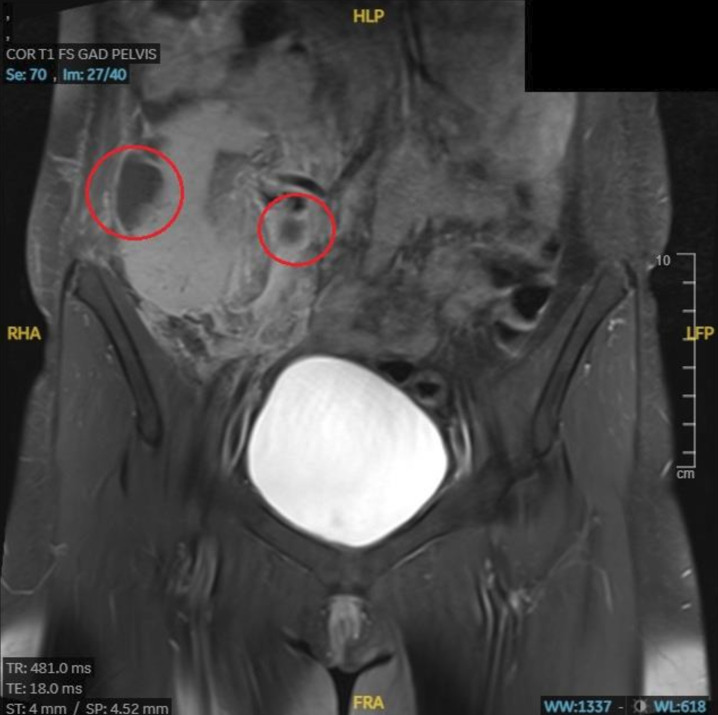

Lump in my side: transplanted kidney or something more?

我身边的肿块:移植的肾脏还是其他什么?